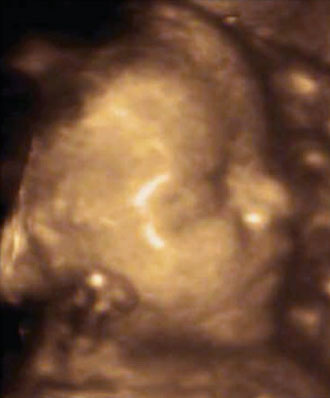

Four Dimensional (4D) Prenatal Ultrasound

Ultrasound uses sound waves to create an image of your baby in your womb. 4D ultrasound uses images from a 3D ultrasound to create a live video effect, like a movie. 4D ultrasound provides you real-time imaging showing your unborn baby’s movement and surface anatomy—you can watch your baby smile or yawn.

In addition to providing an opportunity to see your baby’s face for the first time, a 4D ultrasound may also assist your physician in the identification of certain birth defects that may not show up on a standard ultrasound. Our radiologists review your ultrasound and we send a report to your physician the next day. For the clinical results regarding your and your baby’s health, contact your physician.